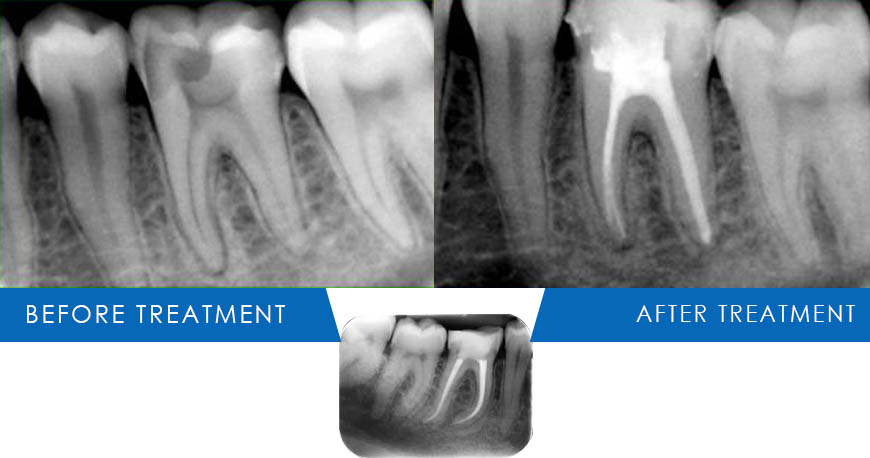

Root Canal Treatment

Best Root Canal Treatment in Kuwait: Your Questions Answered

root canal treatments in Kuwait

Root canal treatments are essential for saving a tooth that has been severely affected by decay or infection. At Medical Consultation Centre (Dr. Thomas' Dental Clinic), under the expert care of Dr. Thomas, we ensure that this procedure is as comfortable and effective as possible.

A root canal is a procedure to treat infection at the center of a tooth (the root canal system). It involves removing the damaged area, cleaning and disinfecting it, and then filling and sealing it.

When the decay reaches the nerve inside the tooth, fillings cannot be performed and then root canal treatment is the only refuge.

Root canal treatment using endo motor has made RCT s less painful, more comfortable, faster and more predictable.